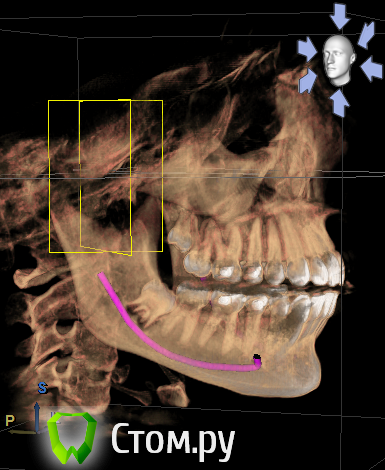

ElenaV Опубликовано 29 июня, 2014 Поделиться Опубликовано 29 июня, 2014 (изменено) Здравствуйте, дорогие доктора! У моей дочери 16ти лет проблема с ВНЧС. При ношении брекетов ей вытягивали нижнюю челюсть, выравнивали прикус и зубы , в частности - клыки выпирающие выравнивали. А через 1,5 года после снятия в одно прекрасное утро не смогла открыть рот. Нам советовали делать лазер, становилось легче. Так было 2 раза. А теперь по утрам, если спит на правой щеке, то челюсть правую заклинивает. Голова сильно болит в висках. Связано ли это с брекетами или другая причина может быть? У нас в Красноярске мы нашли доктора, который собрался нам помочь, поставить шины http://astreja.ru/uslugi/neyro-myshechnaya-stomatologiya. Может ли шина помочь решить эту проблему? В Красноярске выбор докторов небольшой, можно сказать - его нет. И уже просто страшно становится. Читая в интернете об этой проблеме, поняла, что это дело очень тонкое и непростое, испортить жизнь ребенку можно запросто. А еще советуют мануального терапевта. Куда пойти ? Может ли мануальный терапевт решить эти проблемы? Знакомый стоматолог сказал, что если челюсть поправят, то прикус может нарушится. А мануальный говорит - приходите - все исправим, даже снимков ему не надо. Теперь хочу выяснить у специалистов, как все таки поступить. К кому пойти сначала. Очень Вам буду благодарна за совет.Дорогие доктора, можете подсказать, что с суставом? Доктор сказал, что сустав находится далеко от височной кости, т.е. расстояние больше чем норма. Напишите, пожалуйста, что Вы видите на снимке, какую патологию. Вот еще сделала скриншоты суставов: левый и правый Вот еще правый сустав, немножко по другому Изменено 29 июня, 2014 пользователем ElenaV Ссылка на комментарий

Skip Опубликовано 29 июня, 2014 Поделиться Опубликовано 29 июня, 2014 Напишите, пожалуйста, что Вы видите на снимке, какую патологию. Эти КТ, с полуоткрытым ртом и выдвинутой челюстью, мало о чём говорят. У вас там что, уже стоит шина? Ссылка на комментарий

ElenaV Опубликовано 30 июня, 2014 Автор Поделиться Опубликовано 30 июня, 2014 (изменено) Эти КТ, с полуоткрытым ртом и выдвинутой челюстью, мало о чём говорят. У вас там что, уже стоит шина?Шины еще нет, мы сходили на прием, советуют ставить шину. Это КТ в 3Д делали с пластиной во рту, сказали - так надо. Что обычно так делают.Может поэтому и кажется доктору, что сустав неправильно в лунке стоит? Доктор сказал, что сустав далеко стоит от нормального местоположения. Поэтому выскакивает.Нужно МРТ сделать что бы точно понять? Или КТ переделывать? Изменено 30 июня, 2014 пользователем ElenaV Ссылка на комментарий

Force Опубликовано 1 июля, 2014 Поделиться Опубликовано 1 июля, 2014 с восковым шаблоном это по Маклафлину в ЦС сделано КТ. 1 Ссылка на комментарий

Skip Опубликовано 1 июля, 2014 Поделиться Опубликовано 1 июля, 2014 с восковым шаблоном это по Маклафлину в ЦС сделано КТ. Понятно. Ну тогда и с привычной окклюзией стоило бы сравнить, т.е. два снимка, а вернее три, если добавить макс. открытие рта. 1 Ссылка на комментарий